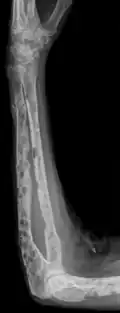

The diagnostic examination of a person with suspected multiple myeloma typically includes a skeletal survey. This is a series of X-rays of the skull, axial skeleton, and proximal long bones. Myeloma activity sometimes appears as "lytic lesions" (with local disappearance of normal bone due to resorption) or as "punched-out lesions" on the skull X-ray ("raindrop skull"). Lesions may also be sclerotic, which is seen as radiodense.[76] Overall, the radiodensity of myeloma is between −30 and 120 Hounsfield units (HU).[77] Magnetic resonance imaging is more sensitive than simple X-rays in the detection of lytic lesions. An MRI may supersede a skeletal survey, especially when vertebral disease is suspected. Occasionally, a CT scan is performed to measure the size of soft-tissue plasmacytomas. Nuclear Medicine Bone scans are typically not of any additional value in the workup of people with myeloma (no new bone formation; lytic lesions not well visualized on nuclear bone scan).

Bone pain affects almost 70% of people with multiple myeloma and is one of the most common symptoms.[2]: 653 [23] Myeloma bone pain usually involves the spine and ribs and worsens with activity. Persistent, localized pain may indicate a pathological bone fracture. Involvement of the vertebrae may lead to spinal cord compression or kyphosis. Myeloma bone disease is due to the overexpression of receptor activator for nuclear factor κ B ligand (RANKL) by bone marrow stroma. RANKL activates osteoclasts, which resorb bone. The resultant bone lesions are lytic (cause breakdown) in nature. They are best seen in plain radiographs, which may show "punched-out" resorptive lesions (including the "raindrop" appearance of the skull on radiography). The breakdown of bone also leads to the release of calcium ions into the blood, leading to hypercalcemia and its associated symptoms.[24]